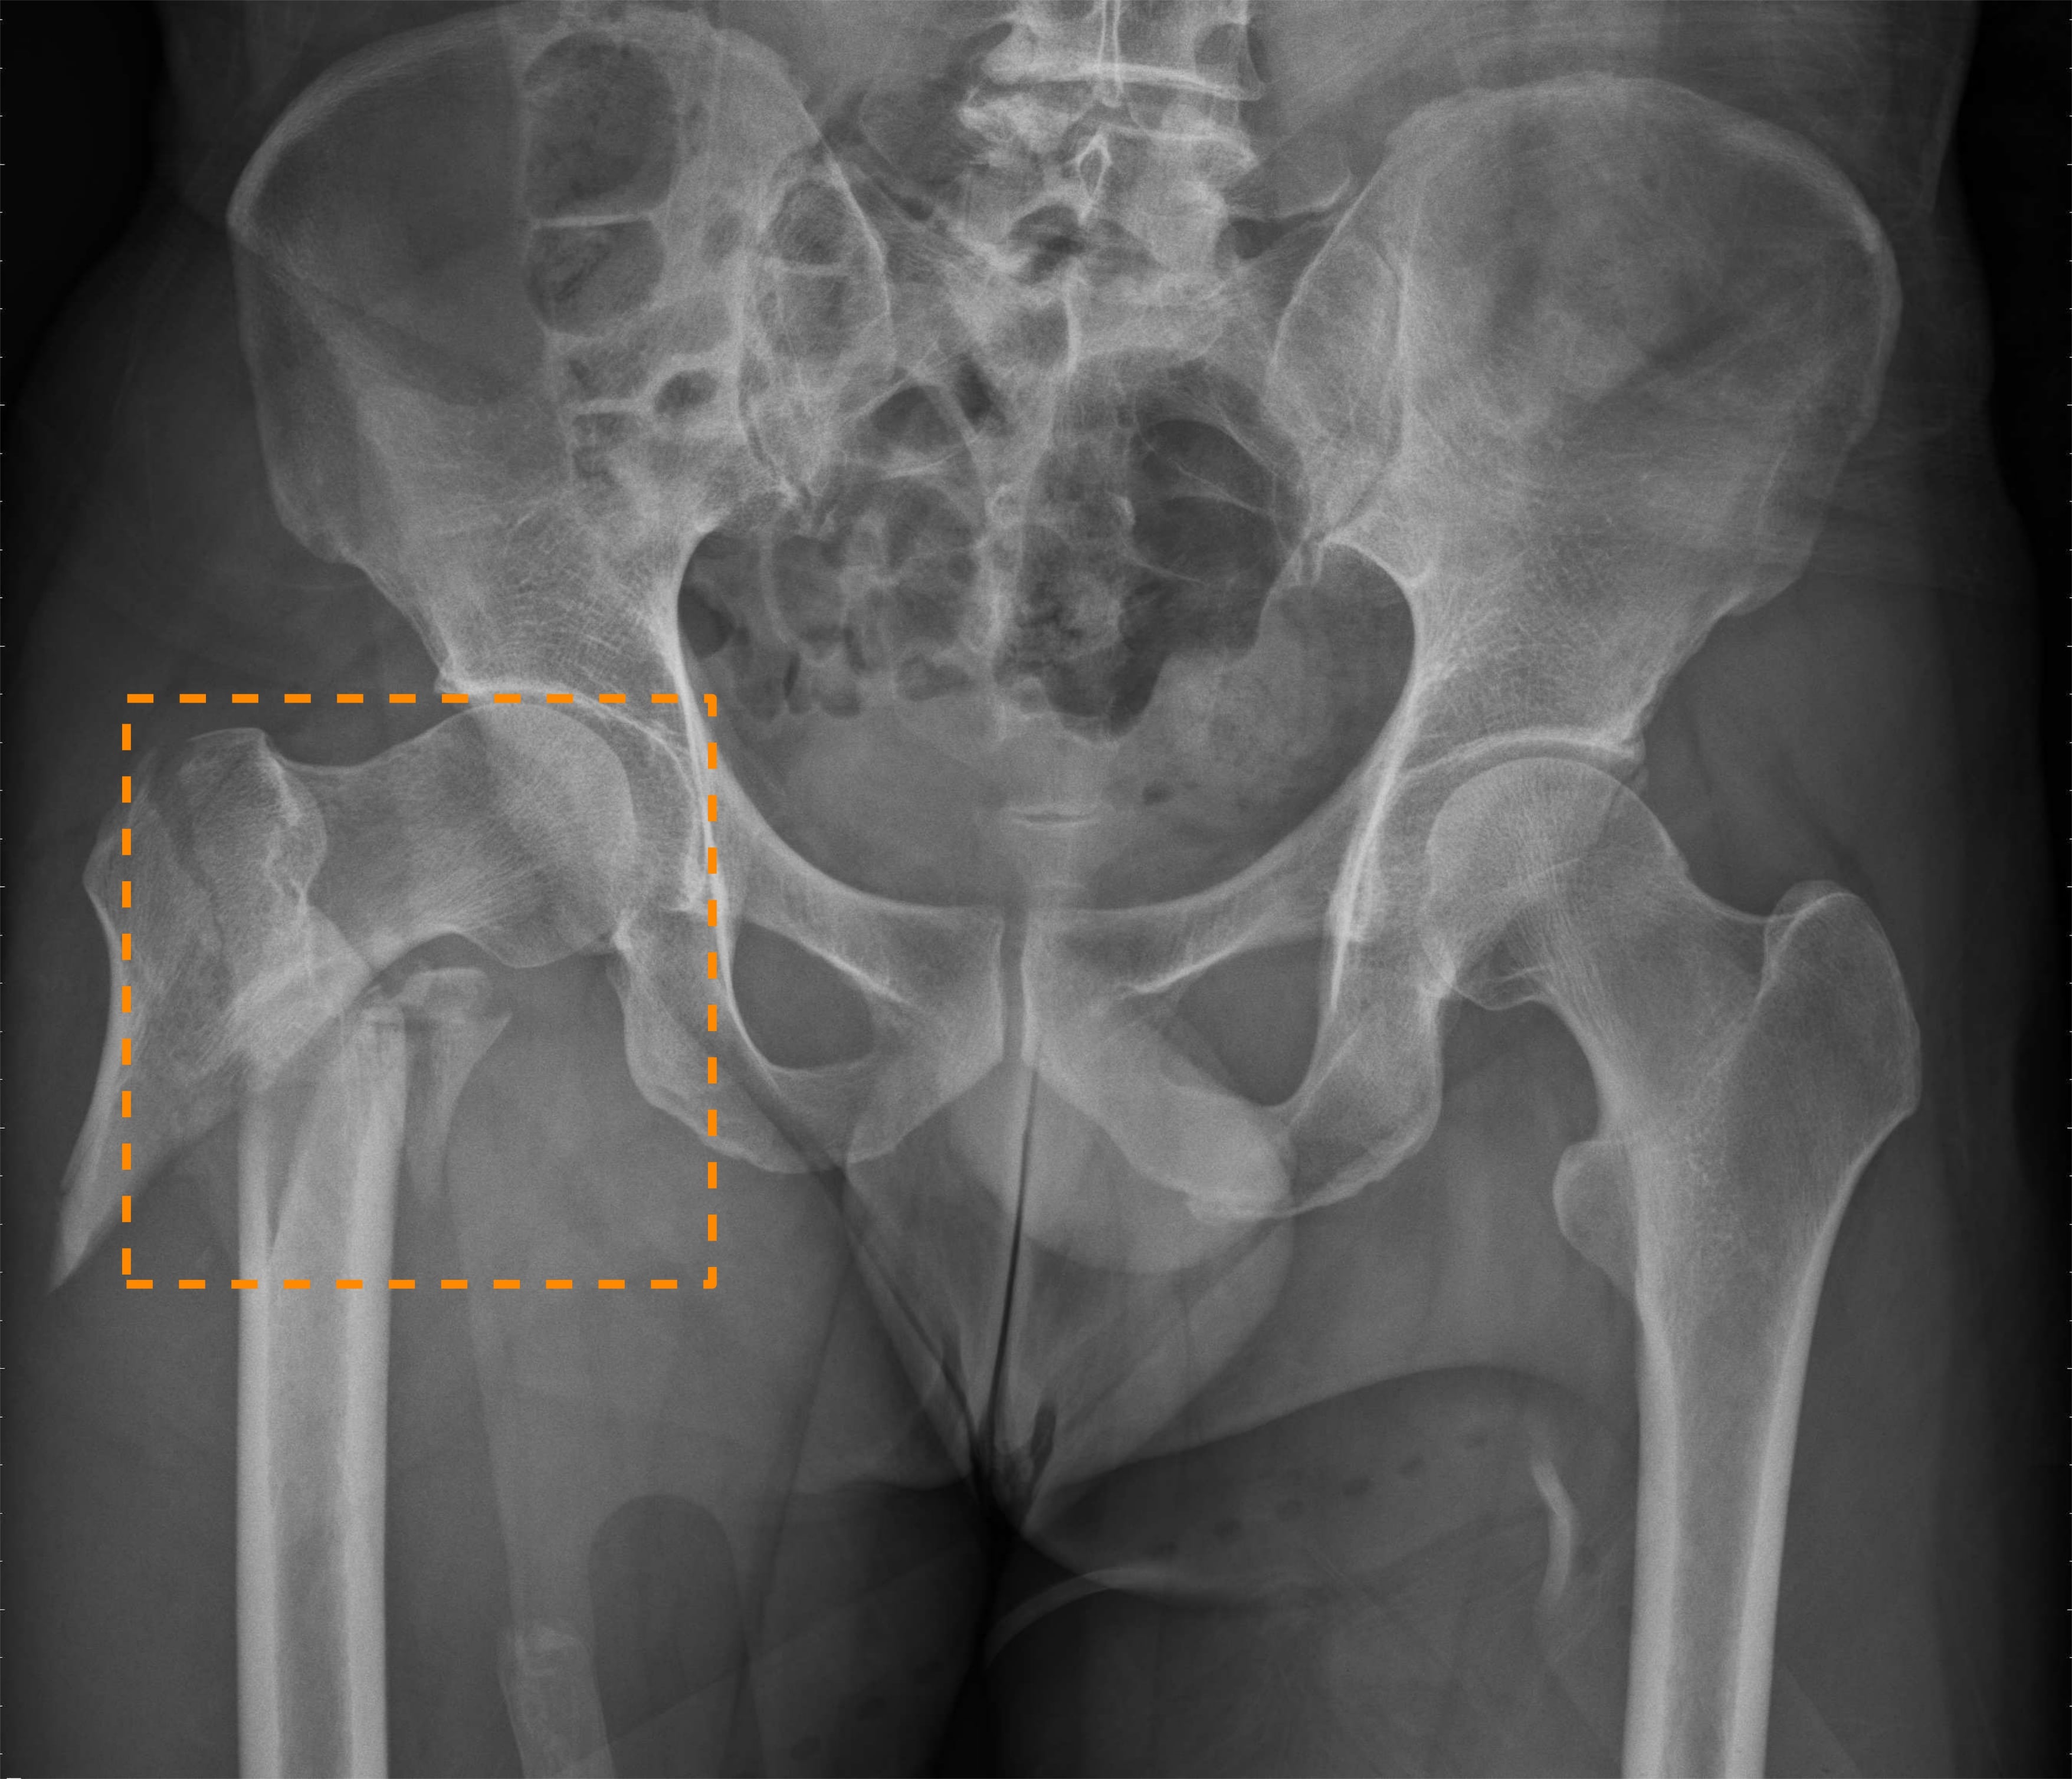

Nonetheless, the above prior work all only focuses on diagnosing hip fractures and does not attempt to classify the more complex pelvic fractures (fractures in three pelvic bones: the ilium, ischium, and pubis). As Fig. 1 illustrates, the makeup of pelvis fractures is much more complex, as there are a large variety of possible types with very different visual patterns at various locations. In addition, pelvic bones overlap with the lower abdomen, further confounding image patterns. Finally, unlike hip fractures, which occur at the femoral neck/head, pelvic fractures can occur anywhere on the large pelvis, both increasing the aforementioned image pattern combinatorial complexity and precluding automatic \acROI extraction based on anatomy alone, such as was done in prior work [4]. Thus, while using \acROI-based classification is even more desirable for pelvic fractures, it is paradoxically more challenging to extract said \acpROI.